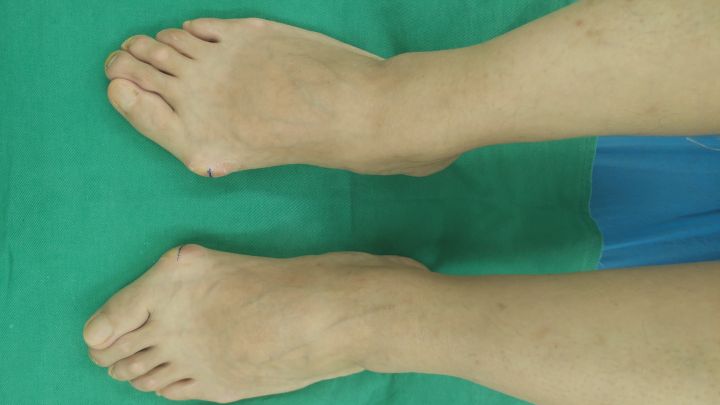

拇外翻-已拇趾向外侧偏斜,伴有局部凸起

接下来我来说说拇外翻的不同,其实拇外翻和痛风还是很容易鉴别诊断,两者的区别还是挺大的。

第一:性别。拇外翻多见于女性,而痛风多见于男性,那么男性朋友如何鉴别自己到底是痛风还是拇外翻呢?

第二:疼痛。拇外翻的疼痛多较轻微,一般是在持续运动或者穿紧致的鞋子后疼痛会稍明显(拇外翻的疼痛程度的拇外翻的轻重程度不成比例),其疼痛多在改善穿宽松鞋子等之后缓解;痛风的疼痛多剧烈,痛风的疼痛多因为吃海鲜、啤酒等高嘌呤食物之后诱发,其疼痛的同时多伴有发热等全身症状。

痛风-第一跖趾关节周围凸起,拇趾不太偏斜

第三:凸起。拇外翻的凸起是因为里面的第一跖骨向内侧偏斜,与第一趾骨向外侧偏斜而组成的犄角,除外凸起,主要还有大拇趾向外侧的偏斜;痛风的凸起是因为痛风石在局部堆积造成的,除外侵犯第一跖趾关节附近外,还有在全身各处沉积,多处出现痛风石结节。